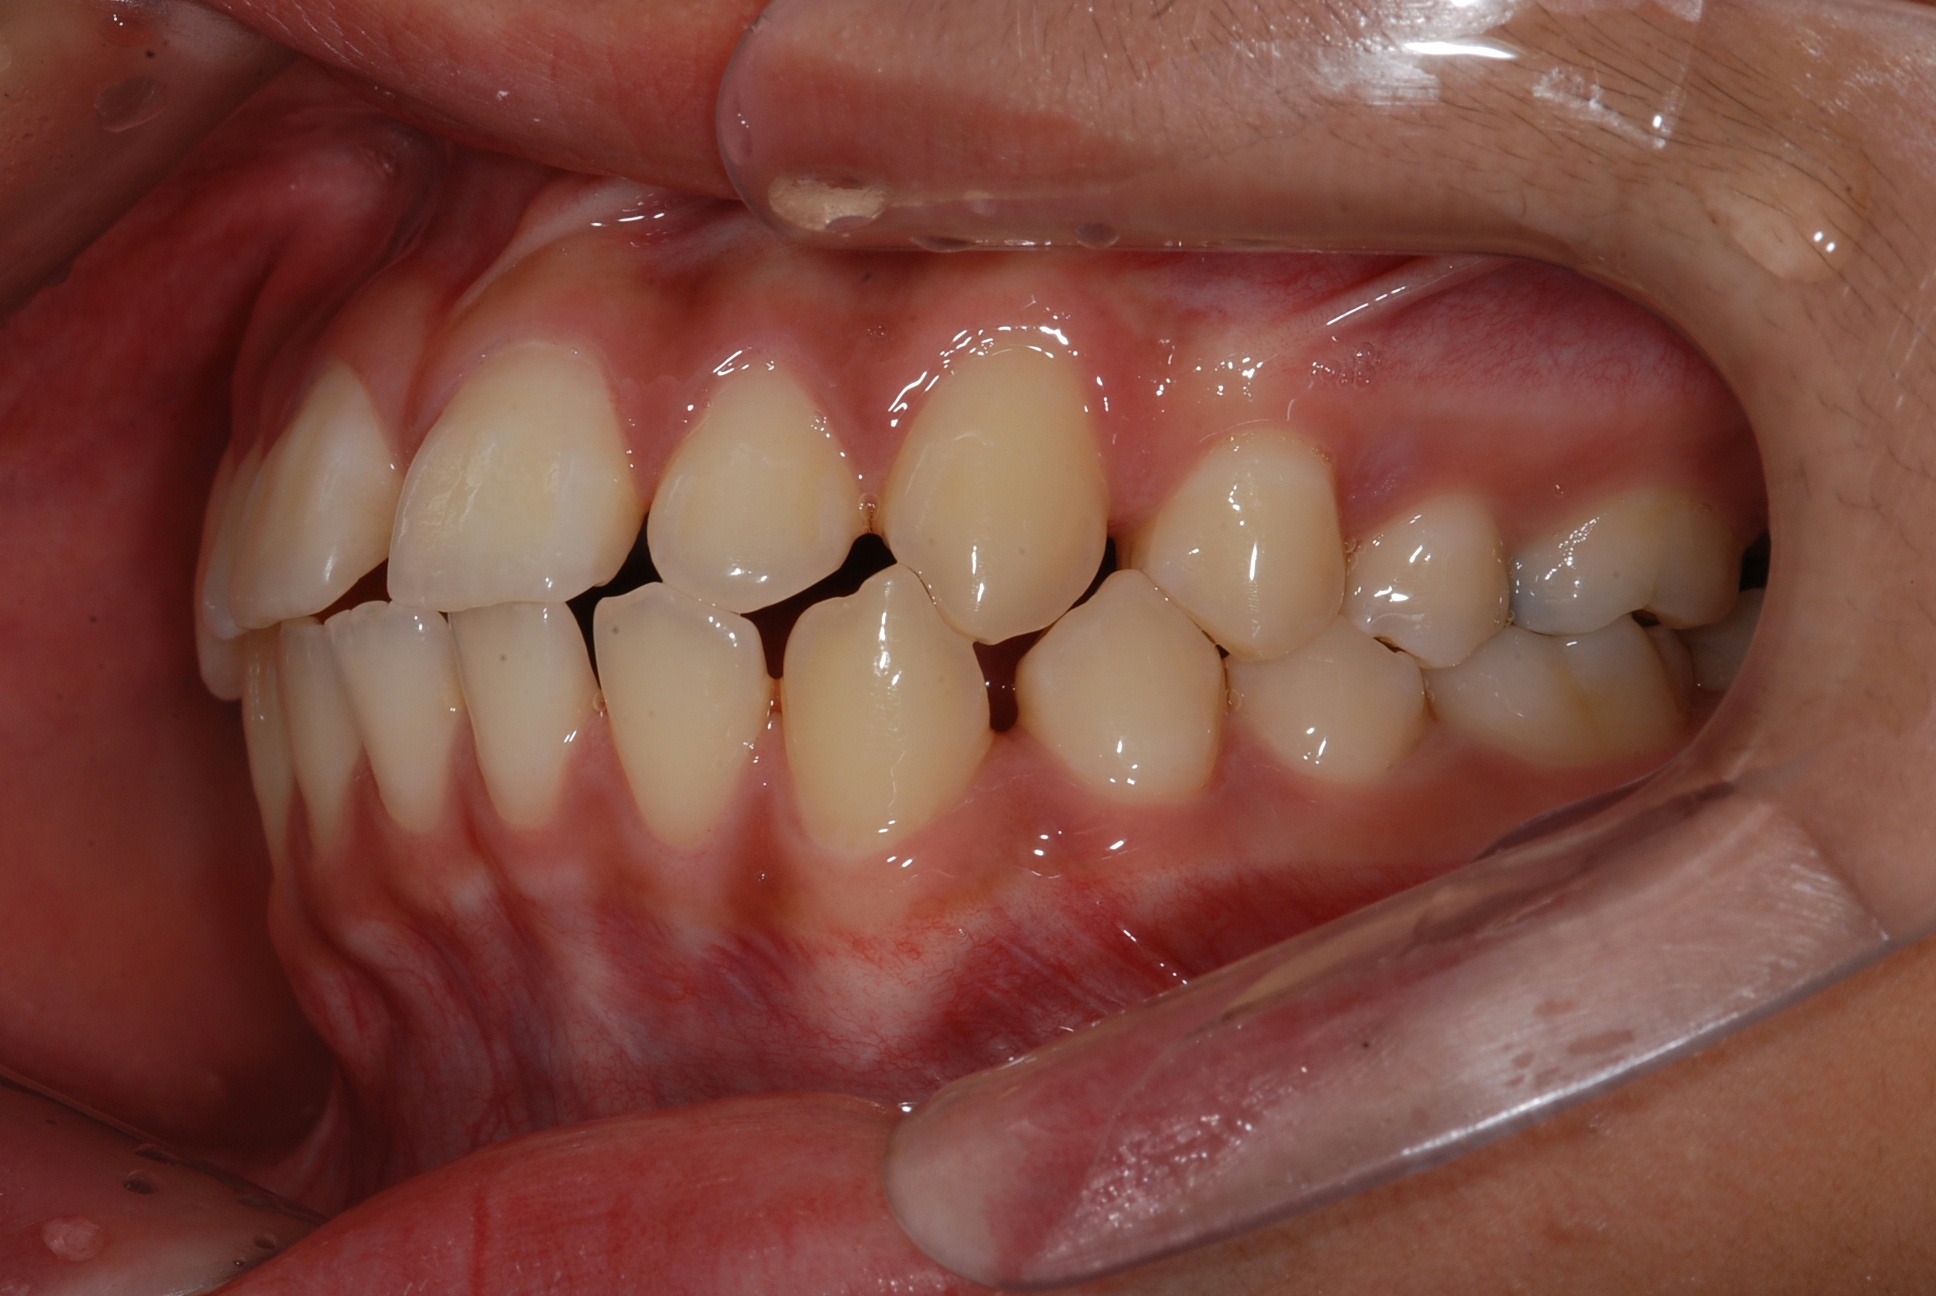

치료 전 사진입니다.